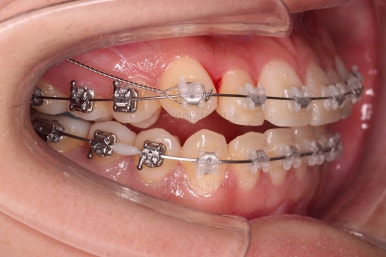

그래서 비발치로 하더라도 본인이 만족할만한 수준까지 입이 나오지 않도록 미니스크류를 병행해서 사용하여 통째로 뒤로 당겨주기로 했습니다.

이번에 사용한 장치는 엠파워 클리어라고 하는 자가결찰 세라믹 장치인데요.

철사를 잡아주는 뚜껑이 브라켓에 달려있어 스스로(자가) 철사를 잡을 수 있는(결찰) 장치라는 뜻인데요. 대표적으로는 클리피씨라고 하는 장치가 있습니다. 클리피는 일본장치, 엠파워는 미국장치라는 차이점만 있고 큰 틀에선느 동일한 장치라고 볼 수 있습니다.

이제부터는 미니스크류를 이용해서 치열을 뒤로 잡아당겨 주면서 뻗침이나 벌어져 보이는 형태를 개선해 줍니다.

점점 느낌이 좋아지는 걸 볼 수 있죠?

중간중간 얼구랏지능ㄹ 보며 함께 치료 목표에 대한 대화를 나누게 됩니다.

입매 괜찮은지, 배열된 느낌, 뻗친 느낌 등등

개선하고 싶은 부분, 개선하려면 추가로 필요한 기간이나 장치 등을 말씀 나누면서 결과를 타협해 나갑니다.